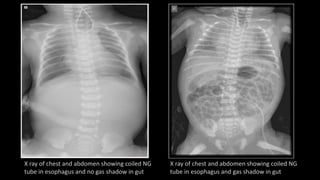

• X ray of chest and abdomen

presence of coiled NG tube in the upper pouch.

in case of fistulae, gas shadow found in stomach and abdomen

in case of no fistulae no gas shadow is seen in stomach or

abdomen.

X ray of chest and abdomen showing coiled NG

tube in esophagus and no gas shadow in gut

tube in esophagus and gas shadow in gut